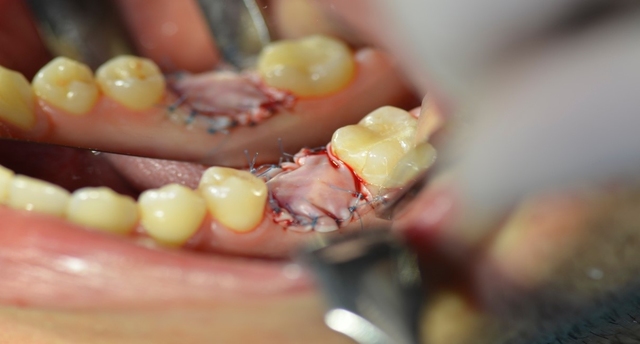

Ryc. 1. Stan kliniczny zęba 36.

Wykonano pantomogram oraz zdjęcie celowane, które ujawniło zmianę okołowierzchołkową przy korzeniu dystalnym. Nie stwierdzono patologii tkanek twardych zębów sąsiadujących z zębem zakwalifikowanym do ekstrakcji, dlatego powzięto decyzję o odbudowie implantologicznej przyszłego braku zębowego (ryc. 1-3).